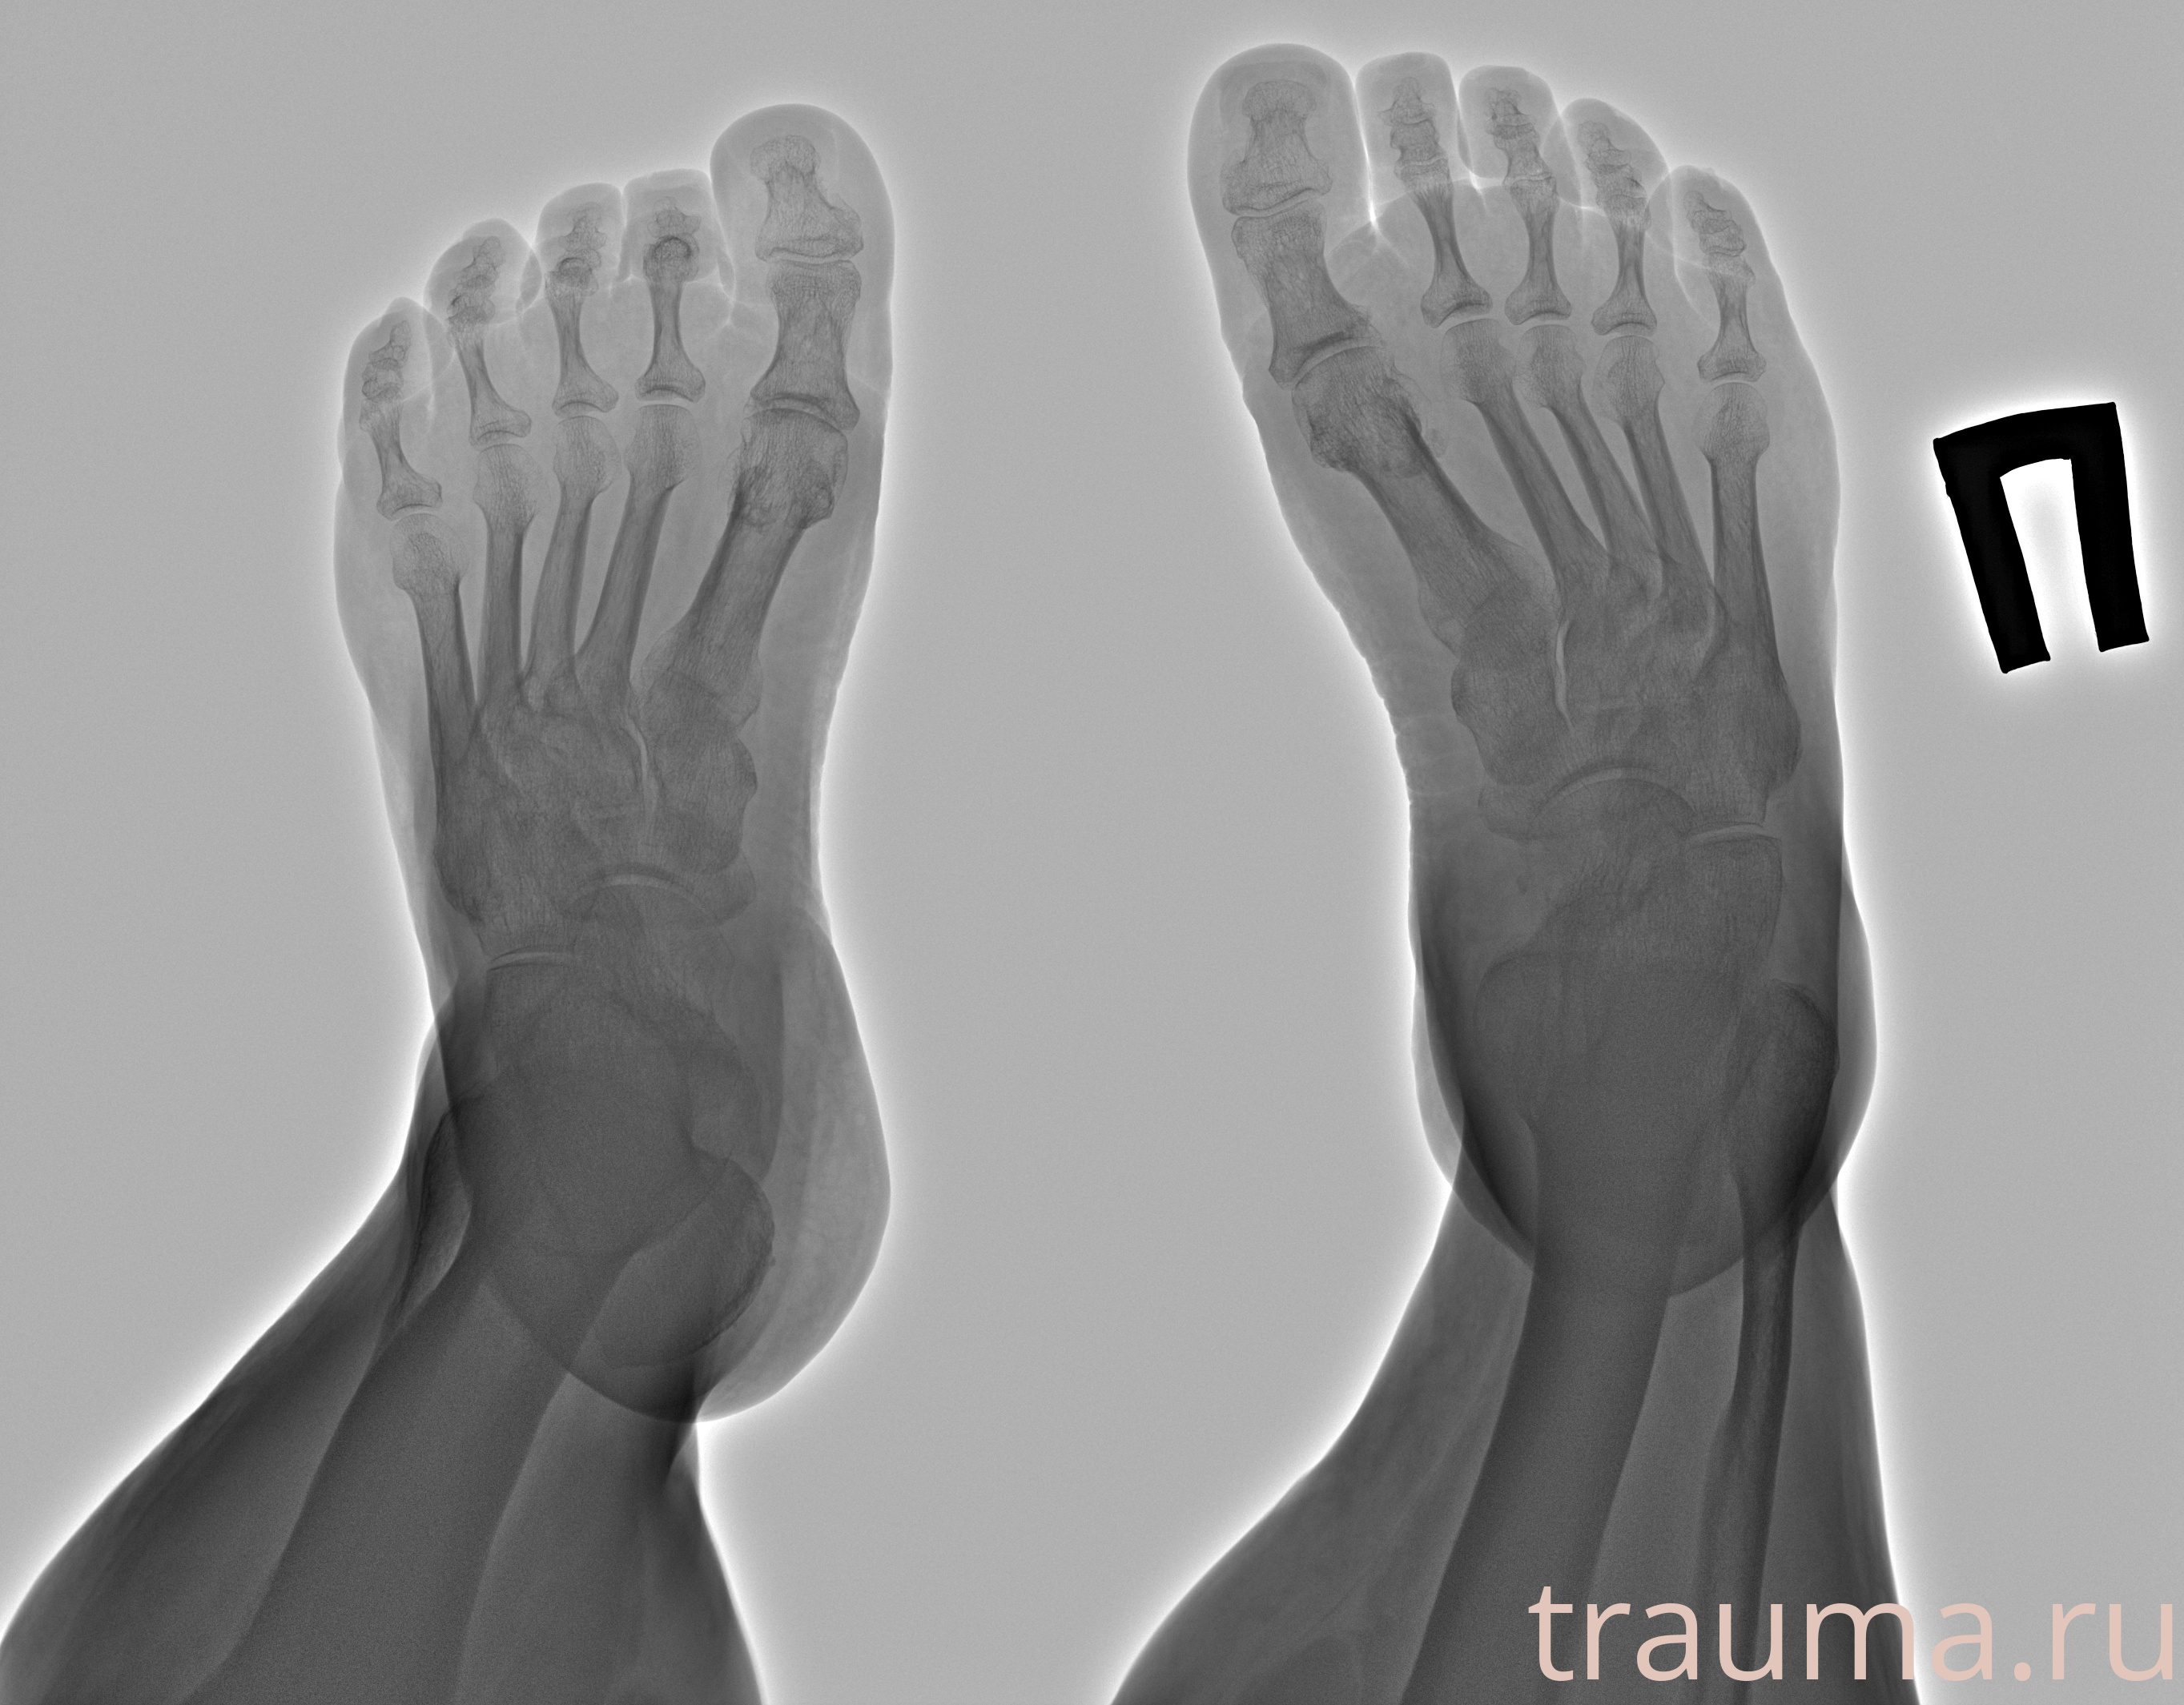

Рентген на дому: по вашему адресу приезжает врач-рентгенолог, травматолог-ортопед с мобильным рентгеновским аппаратом, проводит диагностику травмы или заболевания, делает необходимые рентгенограммы, дает рекомендации по дальнейшему лечению. Получить качественные снимки в домашних условиях возможно благодаря уникальной методике, разработанной МосРентген Центром для института  Склифосовского